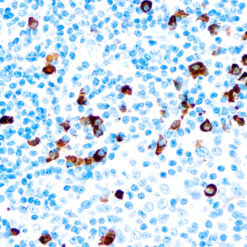

Calponin-1

Multiple isoelectric variants of calponin have been identified but only two molecular weight isoforms exist (34kDa and 29kDa). Expression of the 29kDa form, I-calponin, is primarily restricted to muscle of the urogenital tract, whereas the higher molecular weight variant has been demonstrated in vascular and visceral smooth muscle. Calponin is a calmodulin, F-actin and tropomyosin binding protein, which is thought to be involved in the regulation of smooth muscle contraction. Calponin expression is restricted to smooth muscle cells and has been shown to be a marker of the differentiated (contractile) phenotype of developing smooth muscle.

| Positive Control Tissue | Uterus |